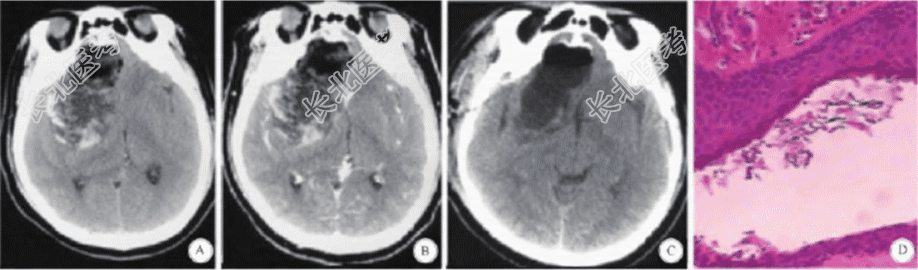

患者,男,58 岁,因“左侧肢体乏力4 年,进行性加重2年”入院。患者4 年前无明显诱因出现左侧肢体乏力,间断发作,不影响正常工作生活,未诊疗;2 年前患者自感左侧肢体乏力较前加重,发作次数较前增多,发作时表现为走路时左下肢拖拽感明显,左上肢上举无力,左手持物不稳,偶有头痛,不伴有头晕、恶心及呕吐,无肢体抽搐,无视物模糊。既往身体健康,无高血压及其他特殊疾病,无家族性遗传性疾病史。入院查体:神志清,双瞳孔等大等圆,直径约3 mm,光反应灵敏,伸舌居中,颈软,左侧肢体肌力四级,无视力视野损害、嗅觉减退等其他阳性体征。颅脑平扫及增强CT检查示,筛窦及右侧前颅中窝不规则混杂密度灶,筛板骨质破坏,边缘尚清,向上达额中叶上部,其内密度不均,可见片状低密度和高密度区,注射对比剂后未见明显强化征象。颅脑MRI示,筛窦及右侧前中颅凹异常信号灶,呈混杂信号。入院诊断为筛窦颅内沟通型巨大病变,考虑畸胎瘤可能。完善术前检查,无手术禁忌,在全麻下行右侧扩大翼点入路肿瘤切除术,术中见颅底骨质缺损,颅底硬膜被肿瘤向上顶起形成肿瘤包膜并包绕肿瘤,切开此硬膜,其内见蜡状、蛋黄样物质并混有短毛发,给予清除,约150 mL;肿瘤内壁为层状结构,呈珍珠样光泽,给予刮除,颅底硬膜塌陷,去除部分硬膜后严密缝合以封堵颅底骨质缺损处,术中地塞米松生理盐水反复冲洗术区,手术顺利。术后地塞米松维持治疗1 周,无无菌性脑膜炎及脑脊液鼻漏出现,术后CT示颅内肿瘤消失,病理诊断形态学结合术中所见(混有少许断毛发),符合皮样囊肿。